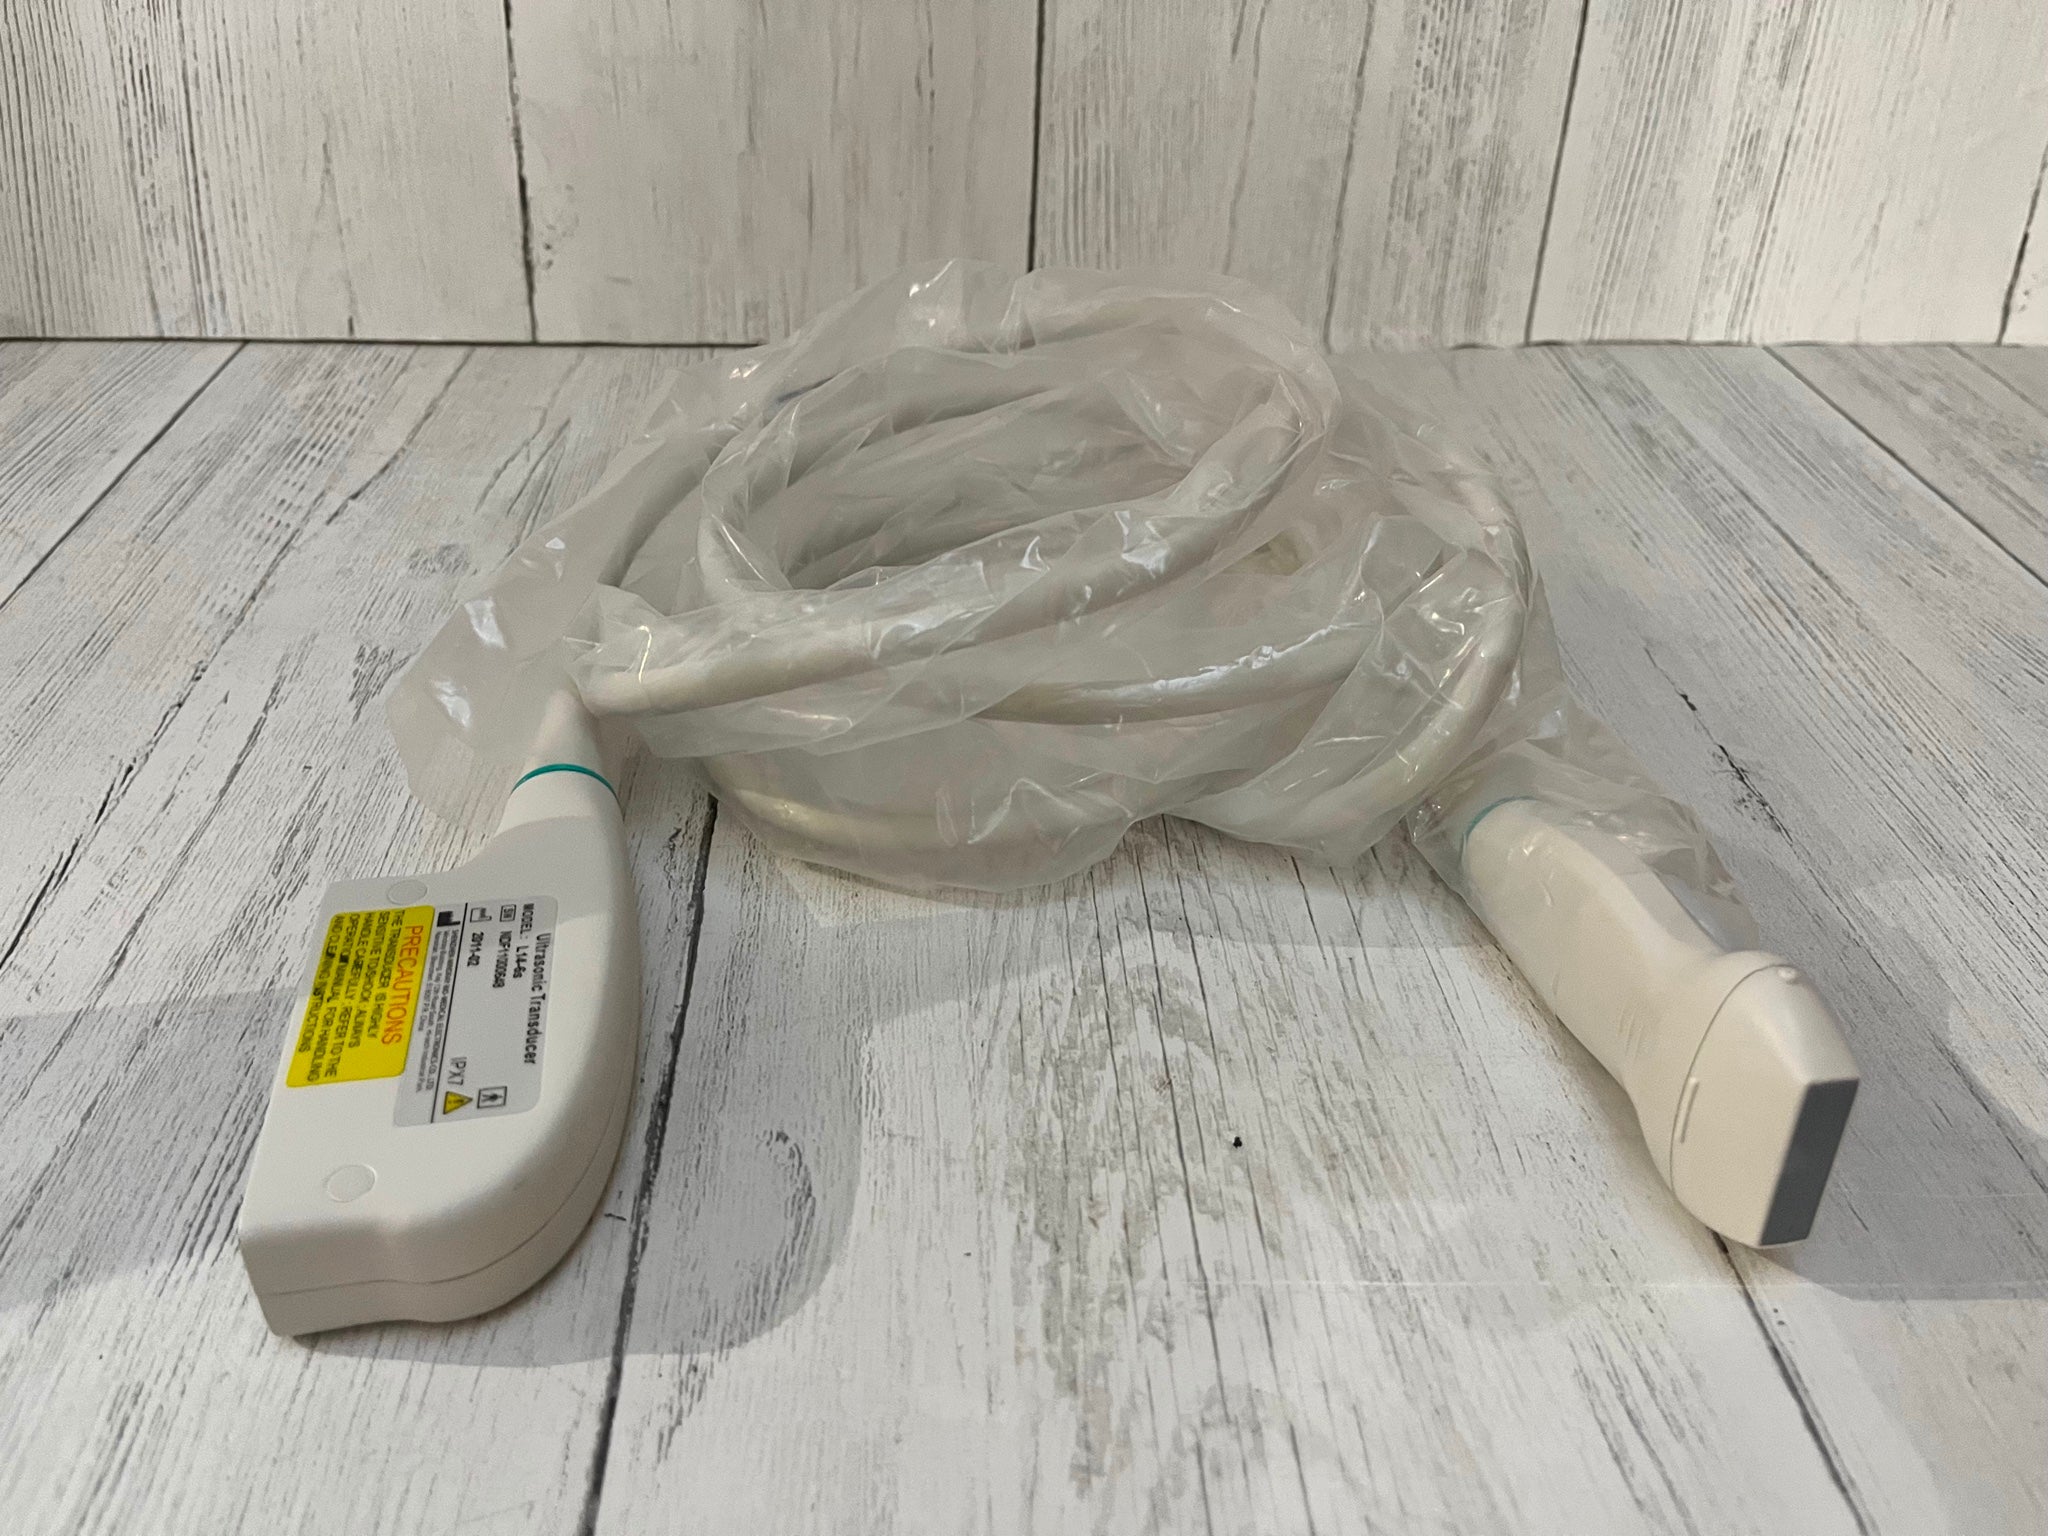

Save $ 317.26

DIAGNOSTIC ULTRASOUND MACHINES FOR SALE

C351 Convexe, Abdominal Transducteur Sonde Pour Sonoscape A6 Ultrasons À Unité

Sale price$ 1,445.26

Regular price$ 1,762.52